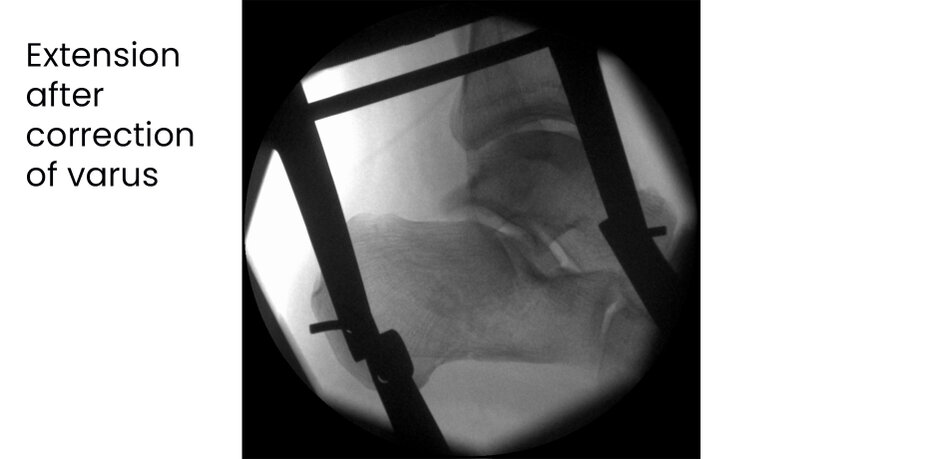

Case 17KL, male, 35y, surgery on day of trauma